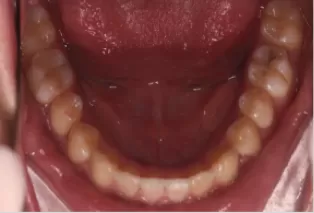

Intraoral photos